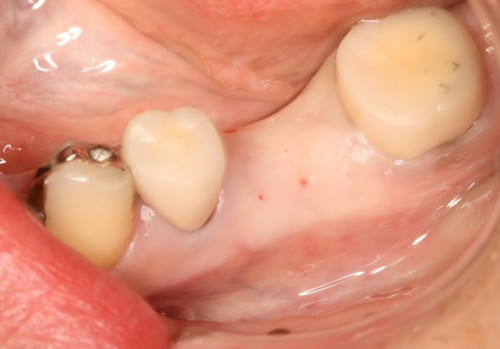

左下奥歯 欠損部 写真

術 前

被せ物装着後